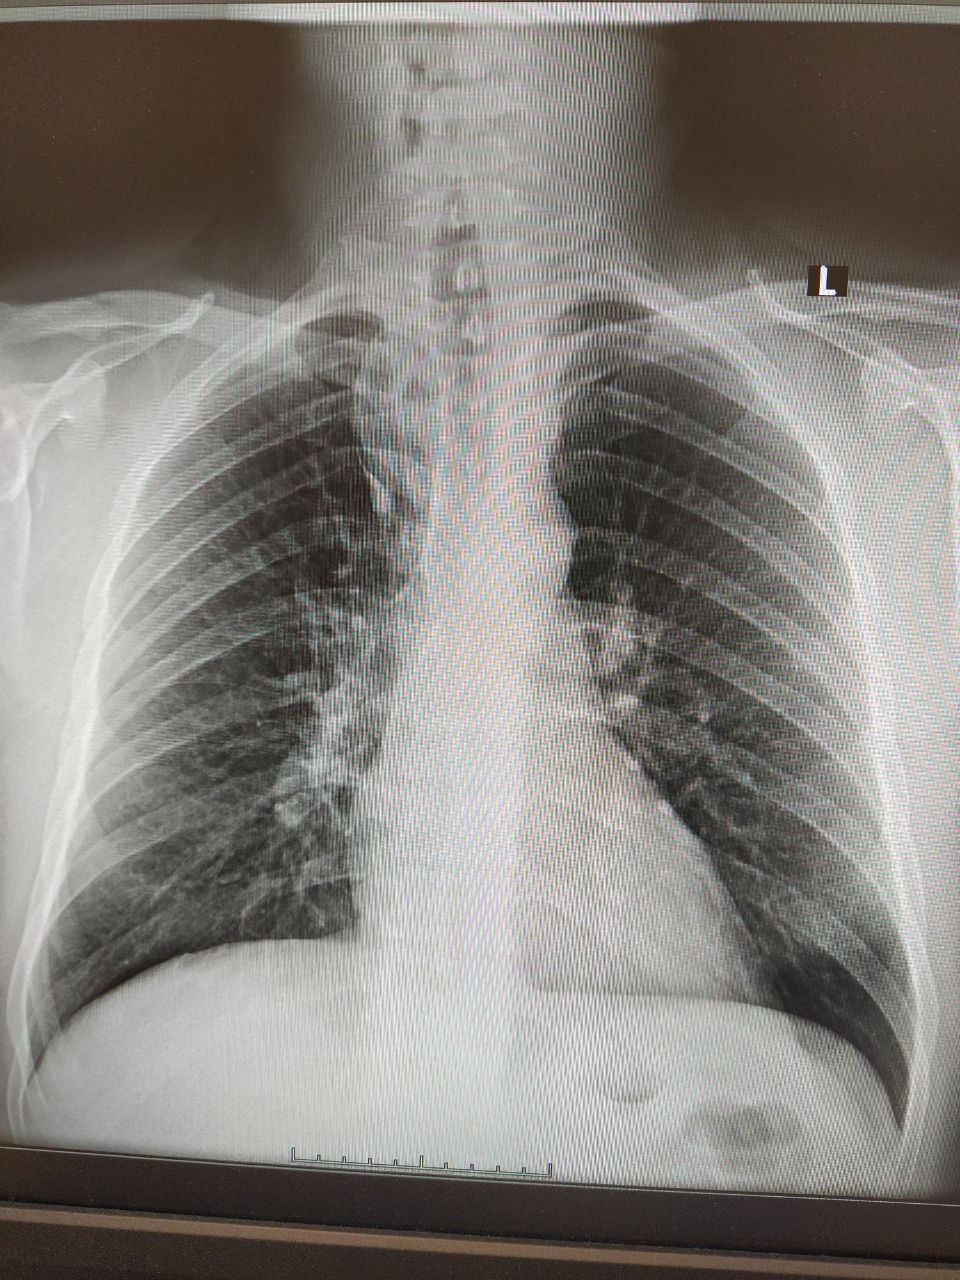

Добавочная доля непарной вены?

Ничего не беспокоит.

Похоже

Там на первом снимке видимо какое образование средостения? Надо боковую р-гр. Дообследование... возможно что то тимомы быть либо лимфоидная что то

Ну да, не исключено, конечно... На добавочную долю всё ж более всего похожа, учитывая отсутствие клиники (при объёме такого размера обязательно имевшийся бы)